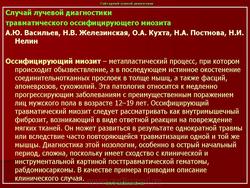

Оссифицирующий миозит

В.М. Давыдова, С.В. Мальцев, Д.Р. Мустакимова, В.С. Валиев

Казанская государственная медицинская академия

Описывается клинический случай редкого заболевания — оссифицирующего миозита — у девочки 11 лет. Представлены данные литературы, касающиеся этого заболевания.

Прогрессирующий оссифицирующий миозит (параоссальная гетеротопическая оссификация, прогрессирующая оссифицирующая фибродисплазия, болезнь Мюнхеймера) — метапластический процесс, при котором происходит обызвествление, а в последующем истинное окостенение соединительнотканных прослоек в толще мышц, фасций, апоневрозов, сухожилий. Является исключительно редкой патологией, хотя первое упоминание об этом заболевании относится к 1648 г., когда впервые Patin описал «окостеневшую» пациентку. Популяционная частота составляет 0,61: 1000 000, то есть около 1 случая на 2 миллиона человек, не отмечается половой, расовой и этнической предрасположенности. Чаще болеют дети в возрасте от 3 до 4 лет, известны случаи дебюта заболевания в возрасте до 3 месяцев.